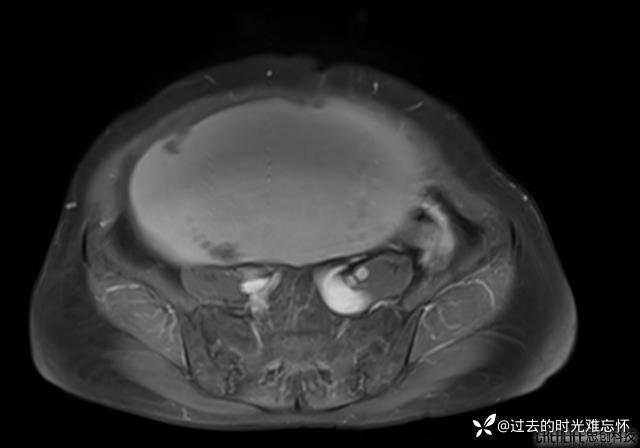

腹大能容5000液;术后腹部好轻松。妙手回春有结果。公布结果。

患者性别:女

患者年龄:65岁

主诉: 发现腹部隆起半年余。无其他明显不适。

浆液性囊腺瘤 (22)